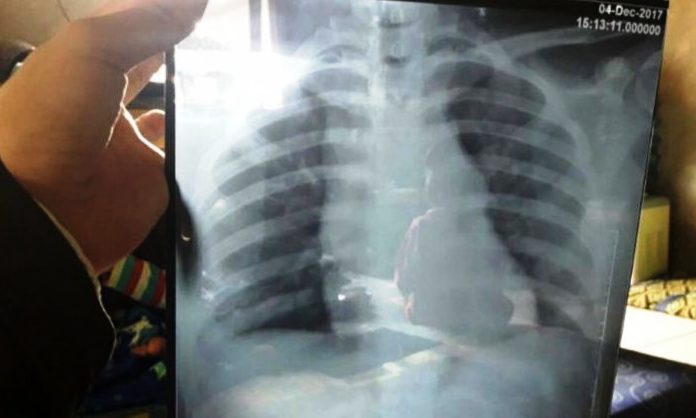

SUMEDANG – Irma Sopiani, 16, gadis asal Tanjungsari yang tak sengaja menelan jarum pentul pada awal Desember lalu, kemarin (19/12) mulai diperiksa di ruang THT RSHS Bandung. Di mana sebelumnya, pelajar SMAN Tanjungsari itu harus menunggu kurang lebih selama sepekan untuk dilakukan pemeriksaan.

Sebelumnya diberitakan, Irma tak sengaja menelan jarum pentul ketika membetulkan kerudungnya di sekolah pada Senin (4/12) lalu. Irma yang juga warga Dusun Ciseureuh Desa Kadakajaya Kecamatan Tanjungsari ini pun, sebelumnya sempat dibawa ke RSUD Sumedang untuk penanganan pertama. Namun dikarenakan keterbatasan medes, gadis ini pun dirujuk ke RSHS Bandung. (red)